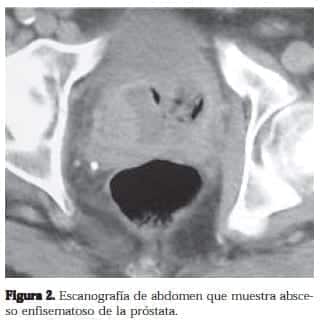

El TAC de abdomen practicado identifica gas a nivel de la luz de la vejiga. Enfermedad diverticular de colon sigmoide no complicada. Y la presencia de un absceso prostático con gas en su interior (Figura 2). Se practicó rectosigmoidoscopia para descartar fístula recto-prostática la cual fue normal.